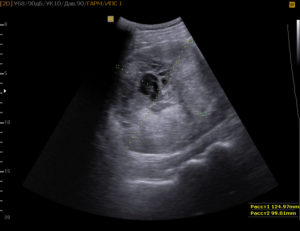

Чаще всего затемнения в почках диагностируют не на УЗИ, а на рентгене

Чаще всего затемнения в почках диагностируют не на УЗИ, а на рентгене. При этом темные пятна носят название «гипоэхогенные» или «участки со сниженной эхогенностью». Если имеются совсем черные участки, их именуют «анэхогенными».

В основном затемнения (гипоэхогенность) могут быть по таким причинам:

- Наличие абсцесса;

- Доброкачественная опухоль;

- Возможное кровоизлияние;

- Онкология небольшого размера.

- Почечные пирамидки также имеют низкую эхогенность и могут быть тёмными на УЗИ.

Совсем черный оттенок имеют:

- Киста;

- Расширенная лоханка, переполненная мочой.